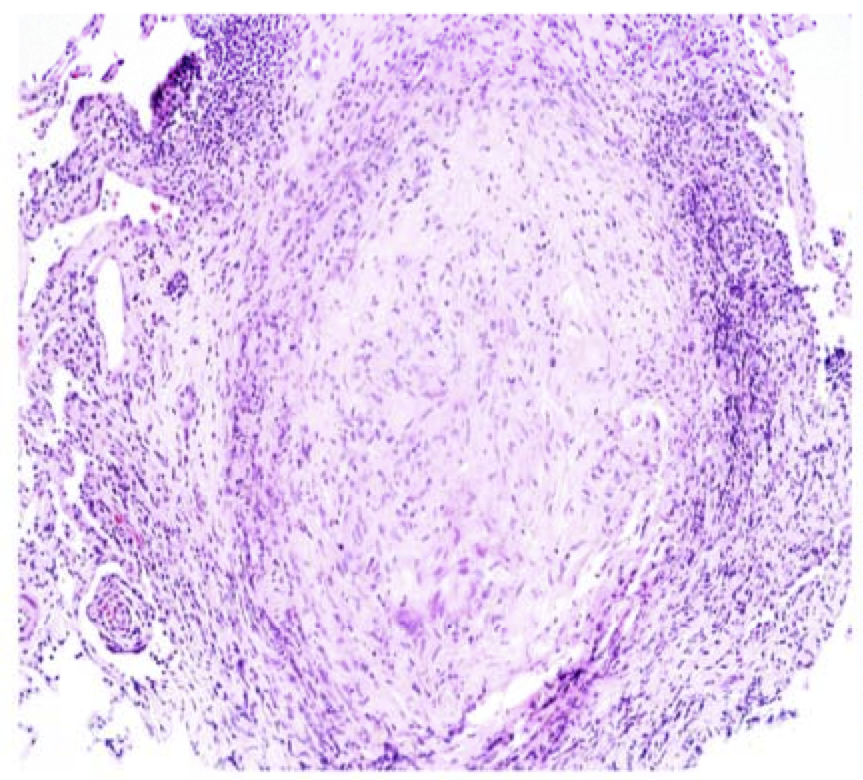

The Agent-based model (ABM) describing tuberculosis (TB) granuloma formation and function in the lung GranSim, the Agent-based model (ABM) describing tuberculosis (TB) granuloma formation and function in the lung, was developed based on four basic concepts: an environment (section of the lung parenchyma), agents (immune cells), ABM rules that govern the agents and their interactions, and the time-step (Δt) used to update events. The attached documentation illustrates the details of how each of these features have been implemented in the form of a pseudocode. The model was first published in 2004 but has been continually updated to include the latest biological information and technological advances. Example of GranSim Time Lapse Simulation 2-Dimensional Granuloma Simulator For more details on GranSim rules and specifications see the documentation file: gransimrules-v2.pdf Parameter Table for GranSim: S1_Table.louisjos-May2021.pdf For more information regarding each individual type of model we use GranSim in (multi-scale, multi-compartment, molecular details, etc) please see our individual publications on those topics at: http://malthus.micro.med.umich.edu/lab/tb.html MULTI-SCALE GranSim Multi-scale Gransim is a computational model that simulates the formation, function and treatment of tuberculosis (TB) granulomas in the lung that builds on GranSim. It is a hybrid model: ordinary differential equations describe the kinetics of molecular interactions and action of antibiotics; partial differential equations describe diffusion of molecules within the lung; an agent-based model captures the actions of individual immune cells and bacteria in a stochastic framework. The model is multi-scale, including molecular and cellular events that produce emergent behavior at the tissue scale. The framework accommodates multiple antibiotics, includes accounting of their pharmacokinetics and pharmacodynamics, and thus can predict the impact of antibiotic treatment on TB granulomas. The model is calibrated and validated against multiple datasets from non-human primates and humans. One multi-scale adaptation of GranSim is GranSim-CBM, which integrates metabolic and agent-based modeling. GranSim-CBM predicts how growth adaptations of Mycobacterium tuberculosis affects granuloma scale outcomes of infection. Antibiotic Drug Treatment in GranSim To see all PKPD equations used in GranSim, view this file: PKPD_eqns.pdf To see all PKPD code files used in GranSim, download and extract this file: GranSim-code-files.zip For a 3D version of GranSim click here.

This granuloma snapshot taken from a Non-human primate from

This granuloma snapshot taken from a Non-human primate from